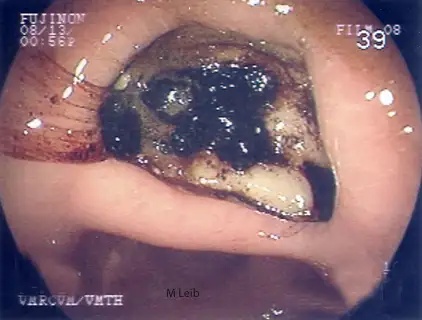

Large gastric ulcer in a 10-year-old Rottweiler. Black clotted blood is adhered to the crater of the large ulcer. The horizontal ridge is the angularis incisura; the antrum is located below the angularis.